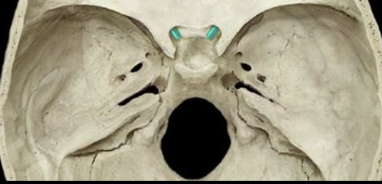

foramen rotundum

knowt flashcard image

foramen spinosum

foramen ovale

optic canal

superior orbital fissure

sphenoid foramina

group of openings/holes in the sphenoid bone; serves as pathways for nerves and blood vessels